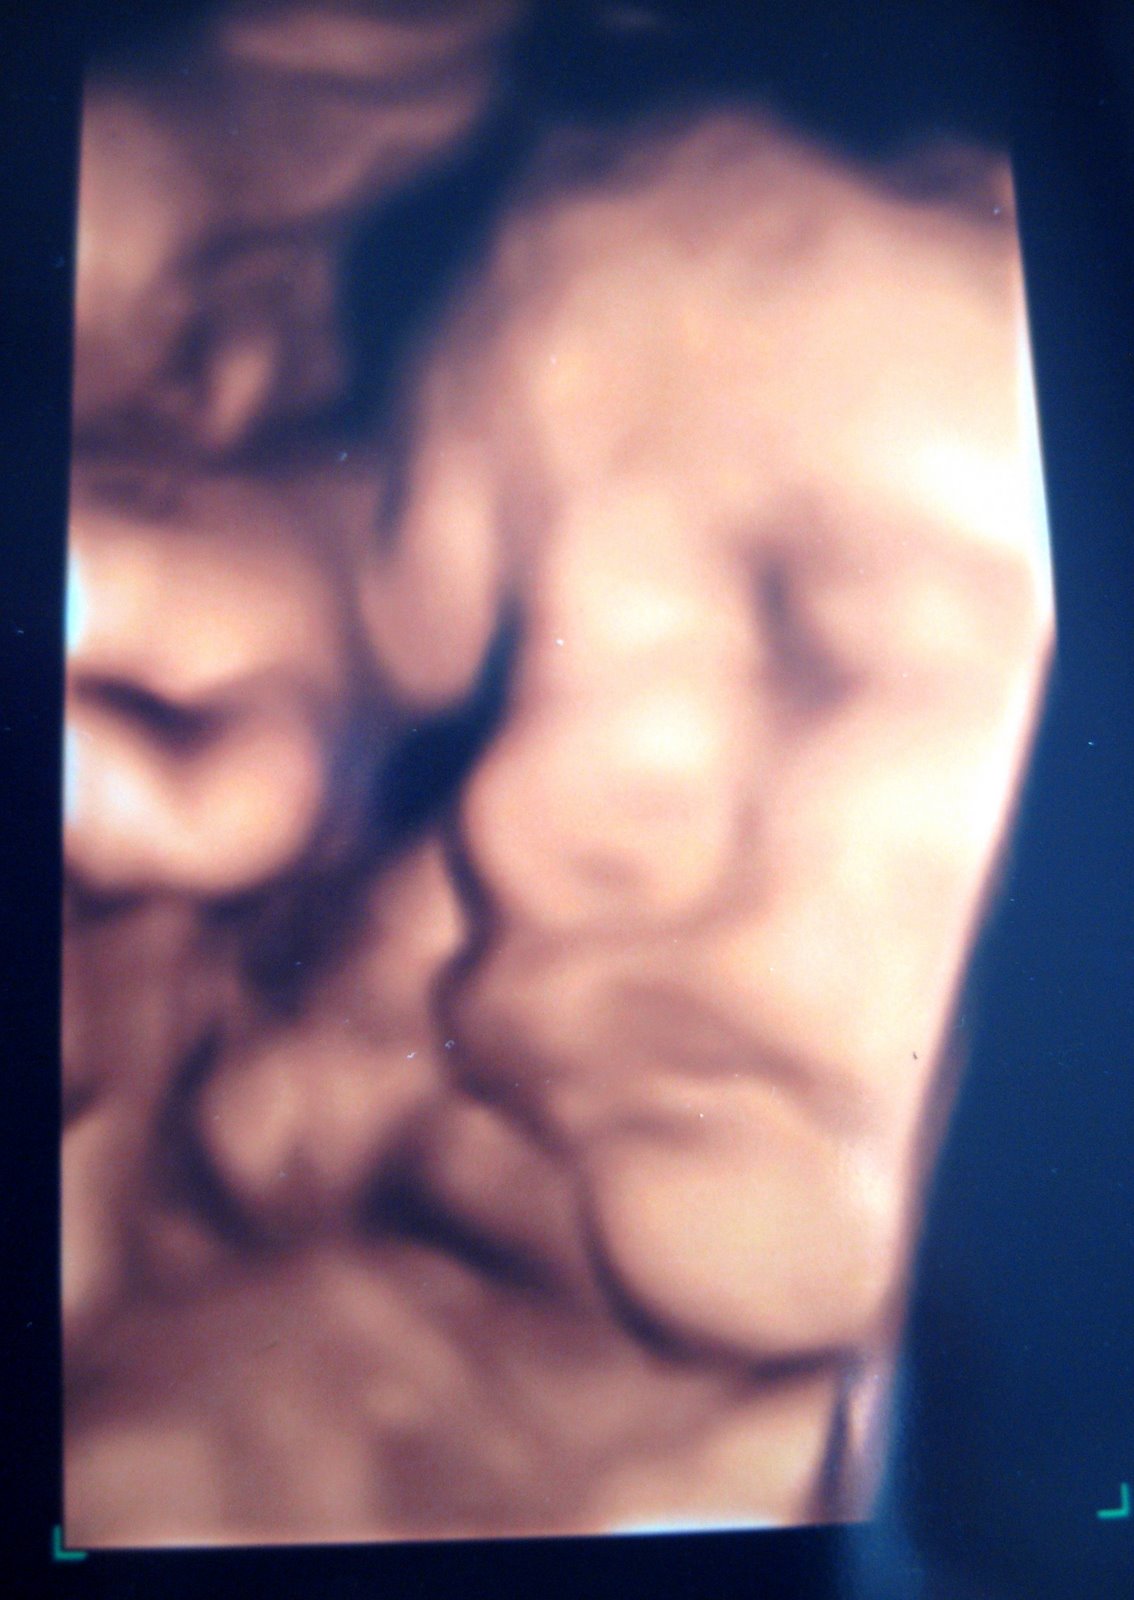

Today as I'm watching the closing ceremonies of the Beijing Olympics on TV (what an interesting 2 weeks), Finn is officially "at term" and probably somewhere between 6 1/2 and 7 pounds - but lets say closer to 6 1/2 shall we? The belly has stretched out even more and my belly button is just about to pop - finally!! I still don't have stretch marks or cankles, but fear not, I still have 3 weeks to go (lets hope not 4)!

The picture of me is at 34 weeks, Melissa (in red) is two weeks behind me at 32 weeks and Gina (in white) is 30 weeks - hello... my belly still looks rather disproportionate but .... then again, according to the ultrasound I had done this morning - Finn weighs about 5.7 lbs right now! Say what?? Dr Kong said she hopes I don't go past my due date because right now she says its looking like an 8lb-er... Where does this kid come from? Have you seen his parents?